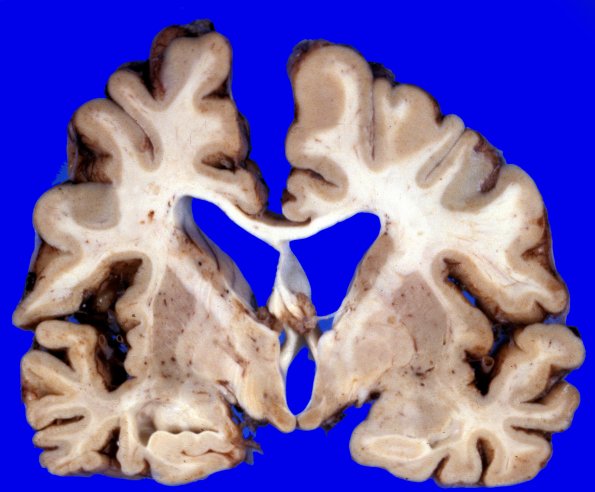

Coronal sections confirm the degree of diffuse cortical atrophy with narrow gyri and wide sulci with a large amount of ventricular dilatation and blunting. The cerebral white matter is diffusely firm to palpation. The corpus callosum is extremely thin.